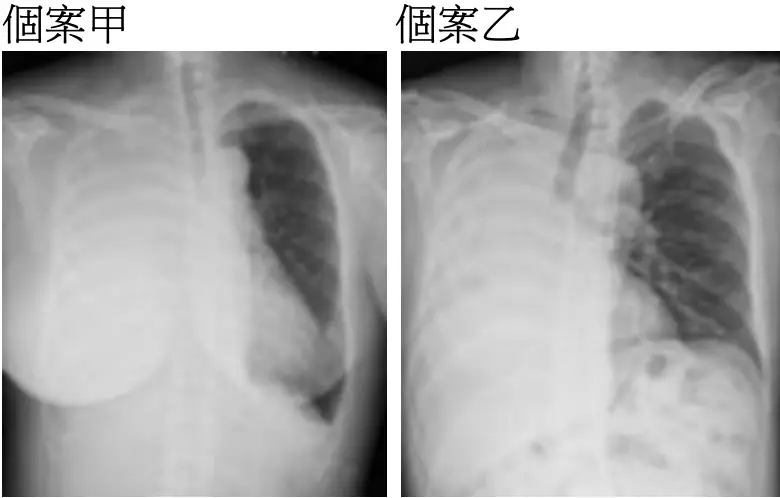

影像分析:

個案甲(右側影像)

- 右側半胸廓高度不透光(whiteness),並見輕度向左側之氣管及縱隔移位

- 右肺邊緣呈平滑弧形,上下緣不透光邊界處呈現弧形界面(meniscus sign),暗示液體分布於胸腔低處

- 肋間距不減小,橫隔未見明顯抬高

以上為典型「大量胸腔積液」表現,因流體為占位性病灶,隨著體腔壓力推擠,可見縱隔結構向對側轉移 (en.wikipedia.org)。

個案乙(左側影像)

- 右側整半胸廓完全不透光,且見氣管及縱隔向右側偏移

- 右側肋間之間距變窄、橫隔抬高、肋骨間距減少

- 無明顯液平面

這些為「整葉或整肺萎陷」(complete atelectasis)典型特徵,因肺容積減少,惹得縱隔結構往同側移動 ([wikidoc.org](https://www.wikidoc.org/index.php/Atelectasis_chest_x_ray?ut